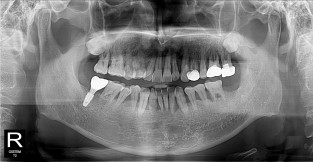

• 2

전체어금니

치료기간 : 2021-11-08 ~ 2022-12-22

1. 상기 x-ray 이미지 모두 동일한 해당 의료기관에서 진료한 환자입니다.

2. 상기 x-ray 이미지 모두 동일 인물의 것입니다.

3. 치료 전 이미지는 2021-11-08에 촬영했으며, 치료 후 이미지는 2022-12-22에 촬영하였습니다.

4. 상기 x-ray 이미지 모두 동일 조건에서 환자분의 동의를 받아촬영되었습니다.

* 임플란트 시술은 환자분의 상태(고혈압, 당뇨 등)에 따라 부작용이 있을 수 있으니, 반드시 전문의와 상담이 필요합니다.

* 임플란트 수술 부작용

: 수술 후 출혈, 교합, 통증, 붓기, 염증 등의 문제점이 발생할 수 있습니다.)